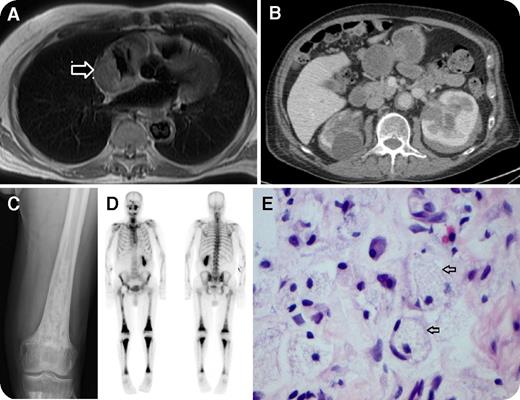

An 80-year-old man was noted to be bradycardic while being transferred to the United Kingdom following neck of femur fracture abroad. He had a 3-month history of weight loss, pruritus, and bone pain. Echocardiogram and cardiac magnetic resonance imaging showed a concentric right atrial mass causing luminal narrowing (panel A, arrow), pericardial effusion, and circumferential infiltration of descending aorta and arch adventitia. Bilateral perinephric soft tissue infiltration was found on computed tomography scan of his abdomen (panel B). Skeletal radiographs demonstrated bilateral patchy sclerosis of the metaphyses of the distal femora (panel C), as well as generalized increased uptake of long bones on nuclear medicine bone scan (panel D). Biopsy of the perinephric tissue revealed infiltration by lipid-laden histiocytes (panel E, arrows; original magnification ×100, hematoxylin and eosin stain), which were strongly positive for CD68 and factor 13a, but negative for S100 and CD1a, confirming the diagnosis of Erdheim-Chester disease. BRAFV600E mutational testing, using pyrosequencing on the perinephric and bone biopsy tissues, was negative.

Erdheim-Chester disease is a rare multisystem non–Langerhans cell histiocytic disorder. Symmetrical long bone osteosclerosis sparing the epiphyses and axial flat bones is the commonest manifestation of the disease. Cardiac involvement is present in about a third of cases. However, a large atrial mass with impending superior vena cava obstruction is relatively uncommon.